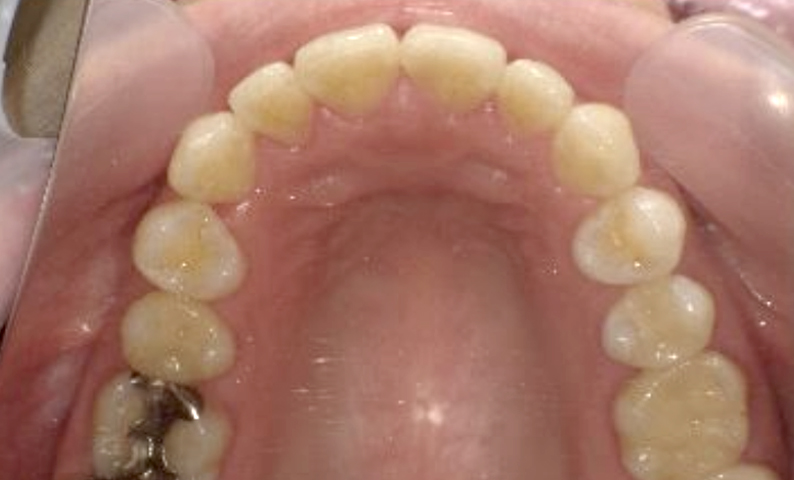

症例_002 上顎だけの部分矯正

治療期間:7ヶ月金額:30万円+税女性前歯のガタガタ上の前歯だけ

| Before | After |